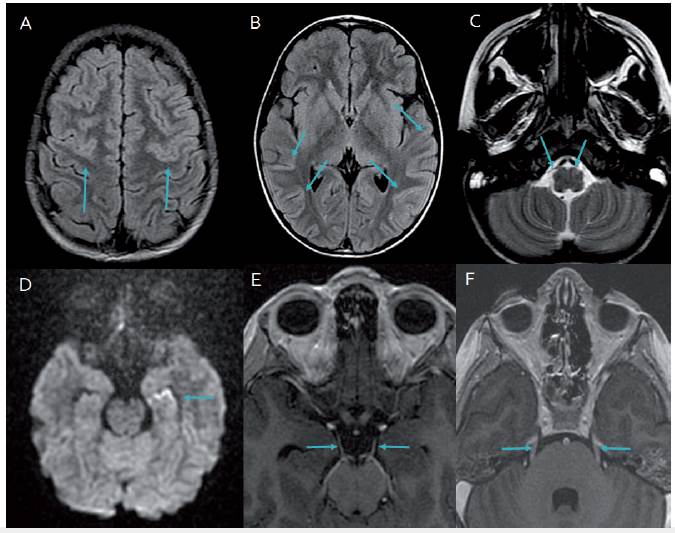

En resonancia magnética cerebral al sexto 6 día de enfermedad, presenta edema cortical mínimo bifronto-parietal (figura 2). Al día doceavo 12 de enfermedad, la resonancia magnética cerebral evidencia realce cortical mínimo bifrontoparietal mediales y temporales, así como compromiso de tallo en región anterior izquierda y leve compromiso de bulbo bilateral a nivel lateral con realce de la señal de pares craneanos simétricos (III, V, VI, VII, VIII y complejo de pares bajos). Se confirma imagenológicamente romboencefalitis mas encefalitis (figura 3). Se identifican bandas oligoclonales positivas, 3 bandas en líquido cefalorraquídeo (LCR), no presentes en sangre. Anticuerpos IgG anti-GQ1b positivos, 1 en 6 400 (VR 1 en 100); anticuerpos antireceptor NMDA negativos (tabla 1). Electroencefalograma 1-2 normal y electromiografía y velocidades de conducción ondas H ausentes. Ondas F discretas. Presencia de polineuropatía desmielinizante aguda. Potenciales auditivos de tallo cerebral con enlentecimiento. Potenciales somato-sensoriales normales.

Imagen de Resonancia Cerebral del paciente que evidencia compromisos: Cortical, Piramides, y de los Pares Craneanos III y V bilaterales.

Figura 3: Imagen de Resonancia Cerebral del paciente que evidencia compromisos: Cortical, Piramides, y de los Pares Craneanos III y V bilaterales.

Nota: A y B, cortes axiales de RM cerebral, secuencias FLAIR. Muestran persistencia de áreas de edema cerebral cortical frontal y temporal (flechas); C, Corte axial T2 muestra edema de la pirámide izquierda comparada con derecha (flechas); D, corte axial con información de difusión DWI, lo que evidencia alteración de la señal en hipocampo izquierdo (flecha); E y F, cortes axiales con información T1 con contraste, que muestra realce de pares craneanos, el par III en E y par V bilateralmente en F (flechas). Fuente: autores.

Esto se correlaciona con los hallazgos radiológicos en resonancia cerebral contrastada a los 12 días, donde se identificó romboencefalitis e inflamación cortico-subcortical, fronto-parietal bilateral y de los potenciales somato-sensoriales. Los potenciales auditivos de tallo mostraban una pobre respuesta en su replicación, lo que confirmaba el compromiso tronco-encefálico 17. Las bandas oligoclonales fueron positivas en líquido cefalorraquídeo, lo que confirmó una reacción inmunológica positiva de antígeno-anticuerpo sérica, que traspasaba la barrera hematoencefalica propia del síndrome de Fisher-Bickerstaff 16.